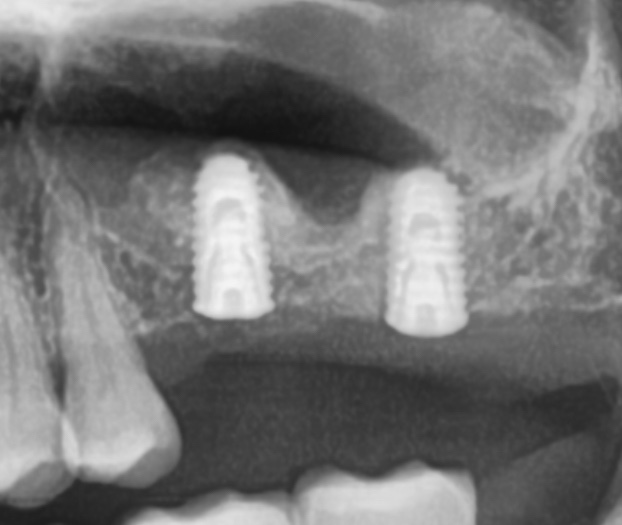

상악동 거상술 및 임플란트 동시식립

저의 임플란트 철학은 가급적 수술횟수를 줄이고, 한 번의 수술로 최대한 할 수 있는 것을 하되, 동시에 성공적인 결과를 얻는 것을 목표로 하고 있습니다.

물론 통상적인 방법으로 상악동 거상술 먼저 시행 후 4-6개월을 기다렸다가 임플란트를 심는 방법도 고려해 볼 수 있었으나, 초기고정에 대한 확신이 있었기 때문에 동시 식립으로 계획하고 무사히 수술을 마치게 되었답니다.